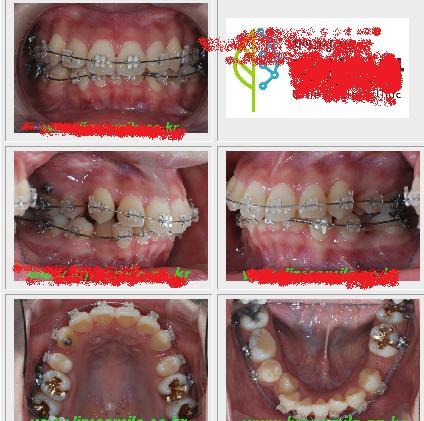

요건 2009년 9월에 찍은 사진임.

5개월만에 덧니랑 이런건 다 배열이 되었고,

내 경우는 윗니를 먼저 배열했음.

그래서 윗니는 치아발치한 공간이 메꿔지지는 않았지만, 가지런해졌음ㅋㅋ

아랫니는 본격적으로 돌입전임ㅋㅋ

그리고 금으로 떼운 모습임ㅋㅋㅋㅋ

그리고 작은 송곳니 썩은건 그냥 병원에서 금메꿔주면서

이정도는 자기네가 해줄수 있다면서 치아색으로 꽁짜로 해줌ㅋ

이건 올해 2010년 3월에 찍은 사진임ㅋㅋ

사진으로 봤을 때 윗쪽보면, 오른쪽치아사이가 덜 메꿔지고 왼쪽은 다 메꿔졌는데,

미니스크류박은쪽과 안박은 쪽 차이에요. 확실히 빨리 메꿔지더라구요.

5월에 되면서 다 메꿔짐ㅋㅋㅋ

아래쪽도 왼쪽 송곳니 들어간걸 끄님어내면서 일단은 가지런하게 만들었어요.

이젠 아랫쪽만 다 메꿔지면 되는 상황임ㅋ